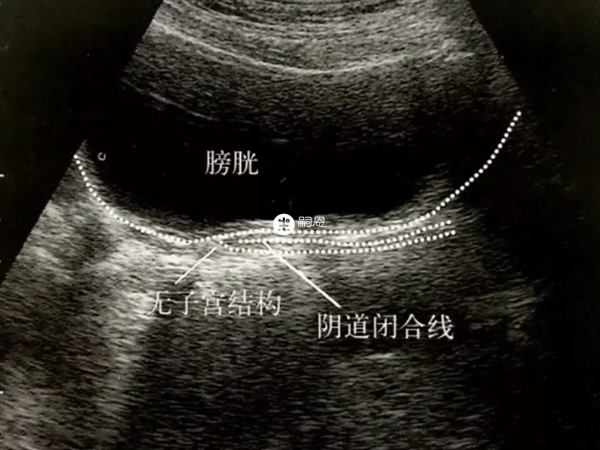

始基子宫多无宫腔和子宫内膜,无月经来潮,常合并无阴道,所以始基子宫类型也分为两种,一种就是有功能的,一种就是无功能的。像这种无阴道的情况就可以在北京协和医院做人工阴道成形手术,也可以顶压法治疗,具体可以前往医院咨询。